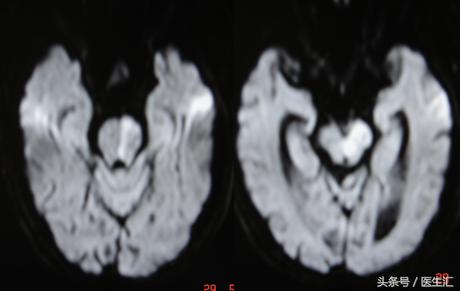

治疗经过:家属同意rtPA溶栓,19时开始rtPA50mg静脉注射2小时后意识转为嗜睡,右侧肢体肌力二级,NIHSS评分19分次日NIHSS评分6分7日NIHSS评分2分(见图8)

MRI示:左丘脑、左枕叶、小脑蚓部、桥脑急性脑梗塞(见图9)